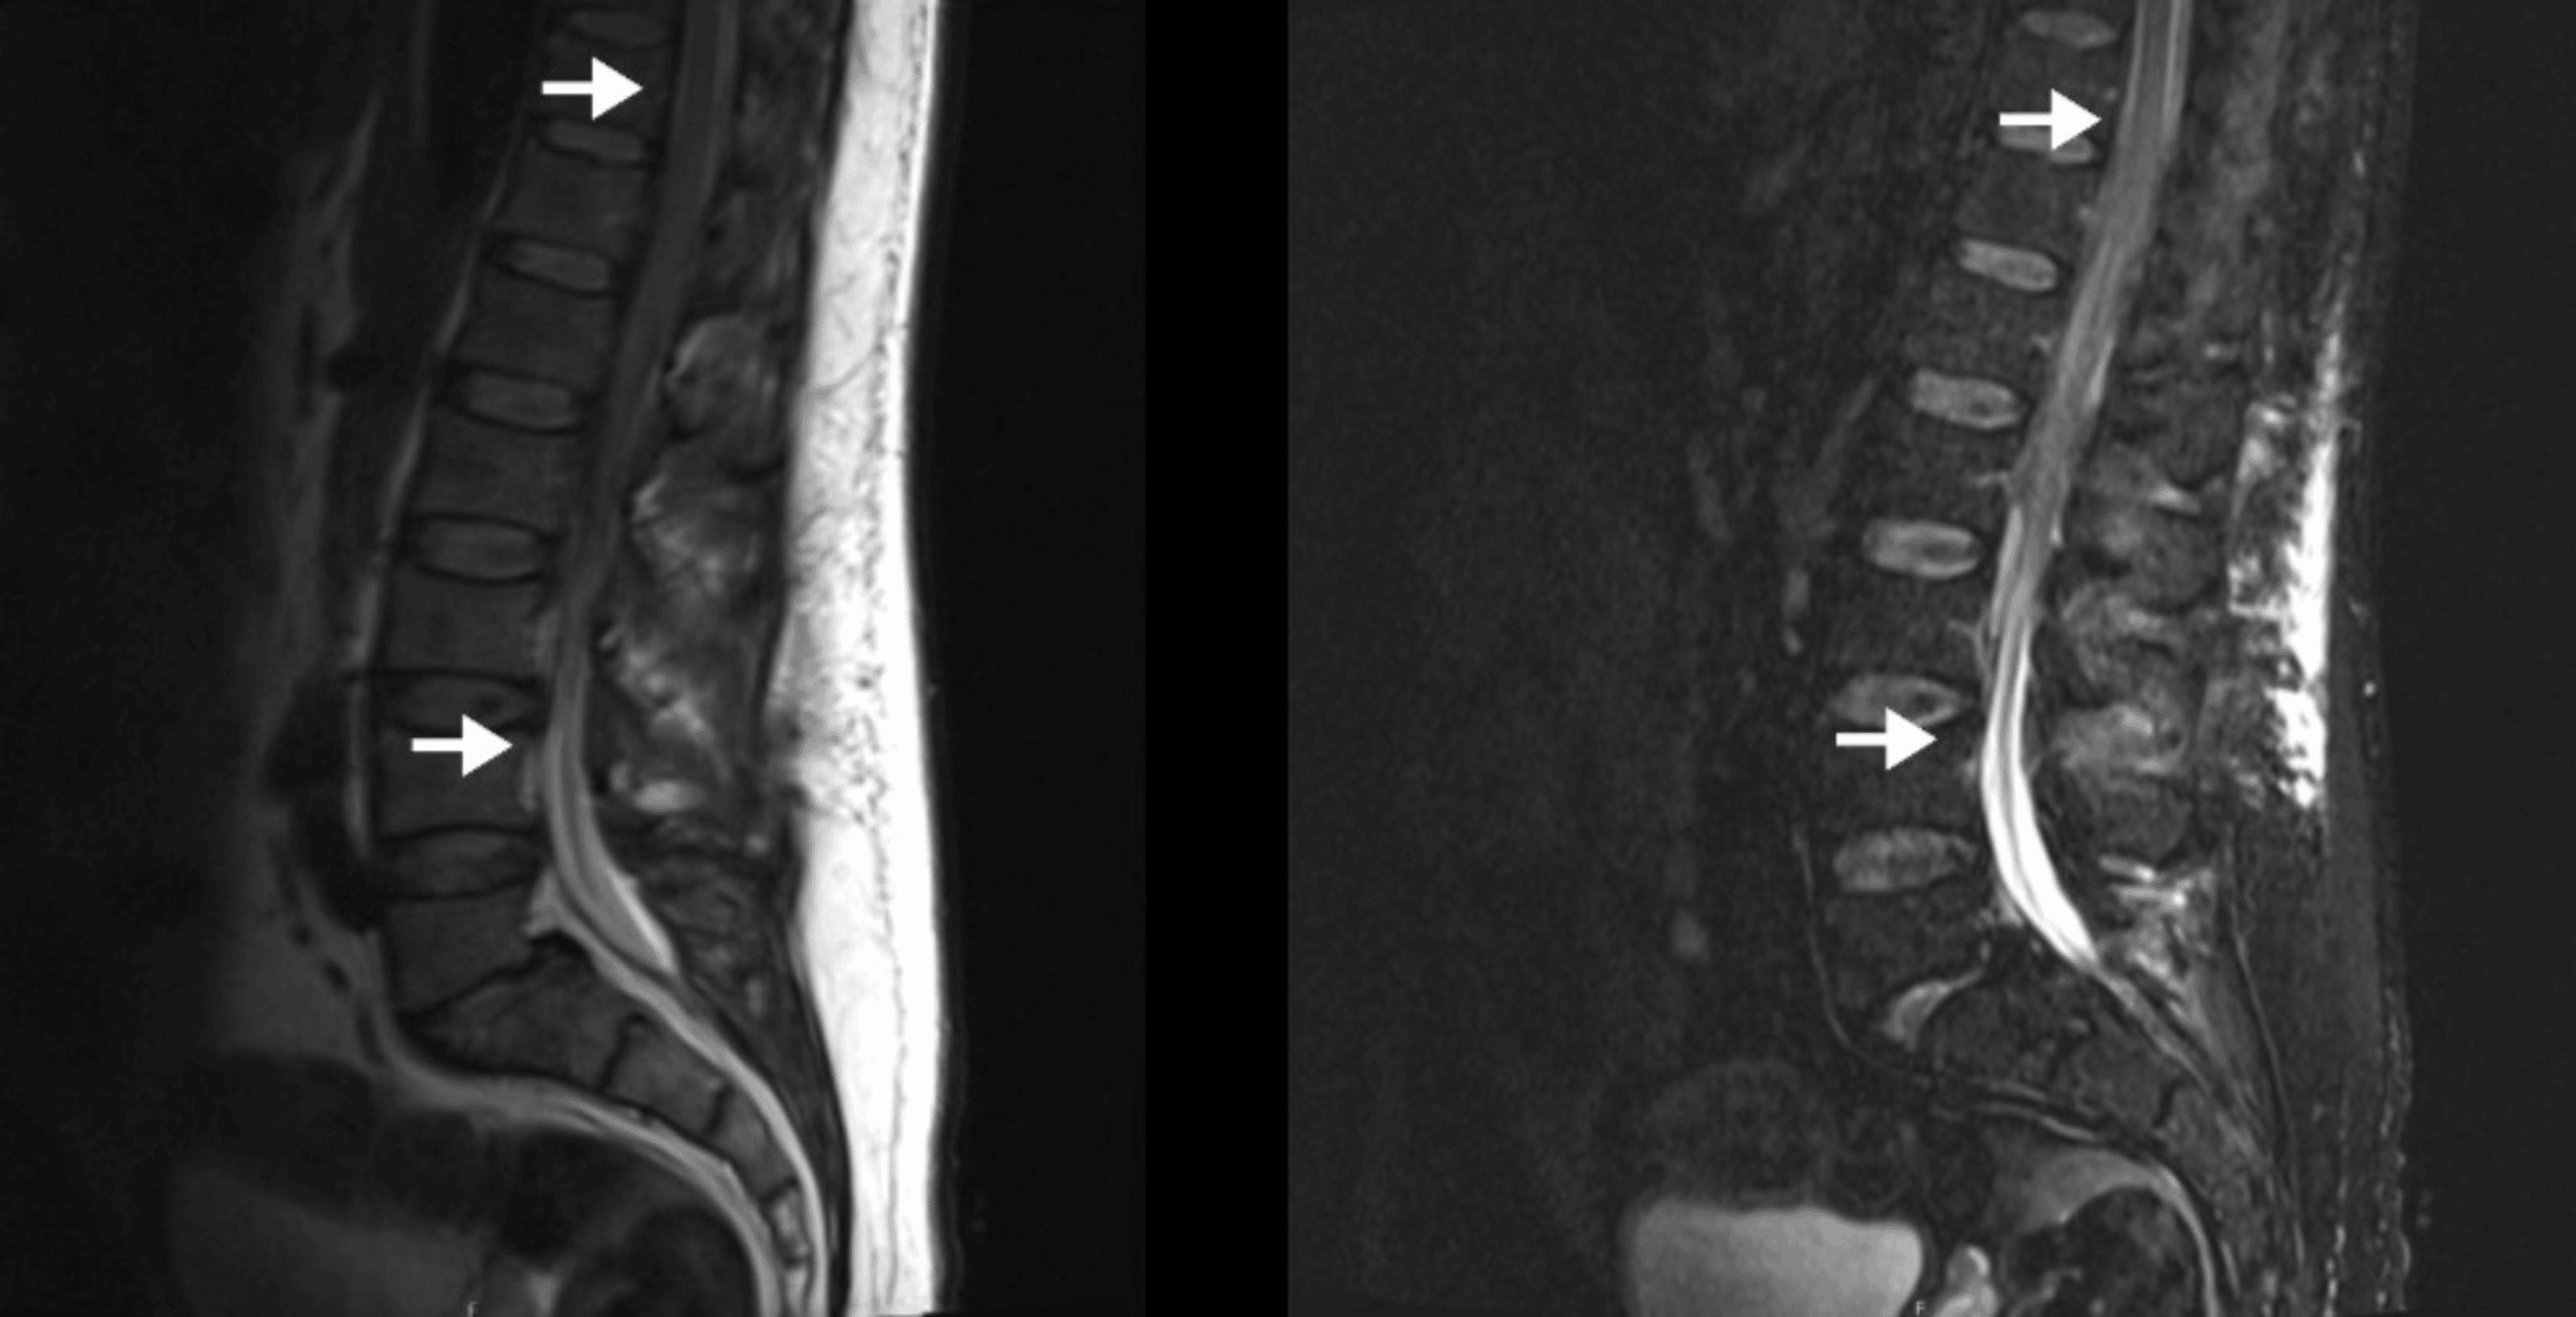

(PDF) Spinal Epidural Hematoma Following Epidural Catheter Removal in a Epidural Catheter Hematoma Spinal epidural hematoma (seh) is a rare but serious condition characterized by the accumulation of blood in the spinal epidural. A lumbar epidural catheter was placed for pain control without complications. Spinal epidural hematoma is a collection of blood in the potential space between the dura and the bone, along the spinal canal. A spinal subdural or epidural hematoma is. Epidural Catheter Hematoma.

(PDF) Spinal epidural hematoma related to an epidural catheter in a Epidural Catheter Hematoma A spinal subdural or epidural hematoma is an accumulation of blood in the subdural or epidural space that can mechanically compress the. Spinal canal (spinal or epidural) hematoma rarely occurs, estimated at 1:200,000 to 1:250,000 obstetric neuraxial procedures and. On the 26th day of hospitalization, three hours after. A lumbar epidural catheter was placed for pain control without complications. Spinal. Epidural Catheter Hematoma.

(PDF) Rapid development of a spinal epidural hematoma following Epidural Catheter Hematoma They are anatomically located in the. Spinal epidural hematoma is a collection of blood in the potential space between the dura and the bone, along the spinal canal. A lumbar epidural catheter was placed for pain control without complications. A spinal subdural or epidural hematoma is an accumulation of blood in the subdural or epidural space that can mechanically compress. Epidural Catheter Hematoma.

(PDF) Spinal epidural hematoma after insertion of a thoracic epidural Epidural Catheter Hematoma Significant bleeding can lead to spinal cord. A spinal subdural or epidural hematoma is an accumulation of blood in the subdural or epidural space that can mechanically compress the. They are anatomically located in the. A lumbar epidural catheter was placed for pain control without complications. On the 26th day of hospitalization, three hours after. Spinal canal (spinal or epidural). Epidural Catheter Hematoma.